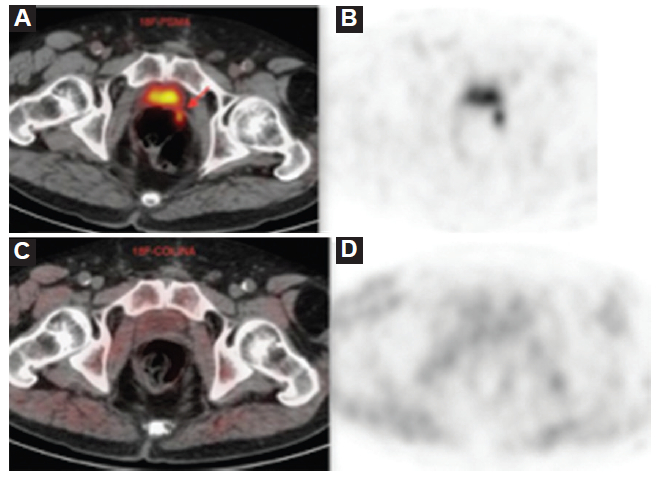

El PSA disparador de la PET/TC mostró una mediana (Q1-Q3) de 3,14 (0,73-8,69) ng/ml. La PET/TC colina mostró una tasa de positividad del 35%, mientras que la PET/TC 18F-PSMA mostró una tasa de positividad del 80%, pero con un PSA disparador ≥ 2 ng/dl la PET/TC 18F-PSMA tuvo un 100% de positivos; mientras que la PET/TC 18F-colina un 55% positivos (Figs. 1, 2 y 3). De las 35 PET/TC 18F-colina negativas, 24 (69%) fueron positivas con PET/TC 18F-PSMA. Todos los PET/TC 18F-colina positivos también fueron positivos con PET/TC 18F-PSMA.